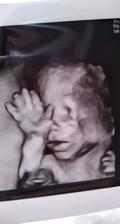

lara_pattinson

6. jún 2019

24tt❤👧👣